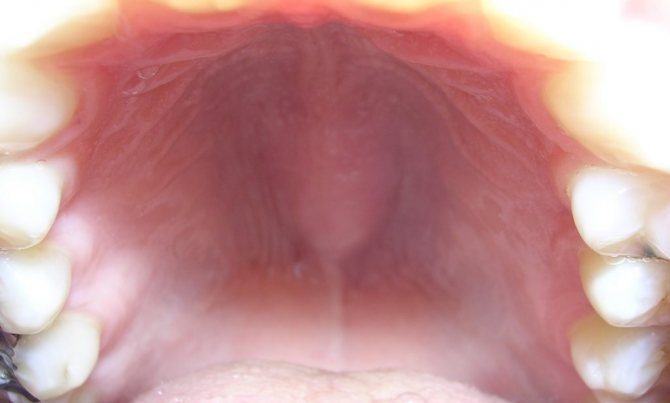

Каждый человек когда-либо сталкивался со стоматологическими заболеваниями. К ним относится не только кариес или парадонтоз. Иногда во рту появляется уплотнение. Оно может быть болезненным или не вызывать физиологического дискомфорта.

Шишка на верхнем небе появляется по разным причинам. При обнаружении новообразований следует обратиться к стоматологу. Врач диагностирует заболевание, объяснит, что это за вид опухоли и назначит лечение. При своевременном визите к доктору прогноз большинства заболеваний благоприятен.

Какая шишка может появиться на небе во рту?

Исходя из происхождения, формы и других клинических особенностей, любая шишка на небе во рту подлежит классификации.

В большинстве случаев шишка на небе формируется из эпителия, мышечных тканей, кровеносных сосудов, органических жидкостей и соединительных структур.

Наиболее распространённый механизм появления шишки на верхнем небе – закупорка сосудов и протоков различного назначения, обусловленная отёком воспалённых тканей. Основную опасность представляет потенциальная угроза их трансформации в злокачественную аномалию, что происходит достаточно редко.